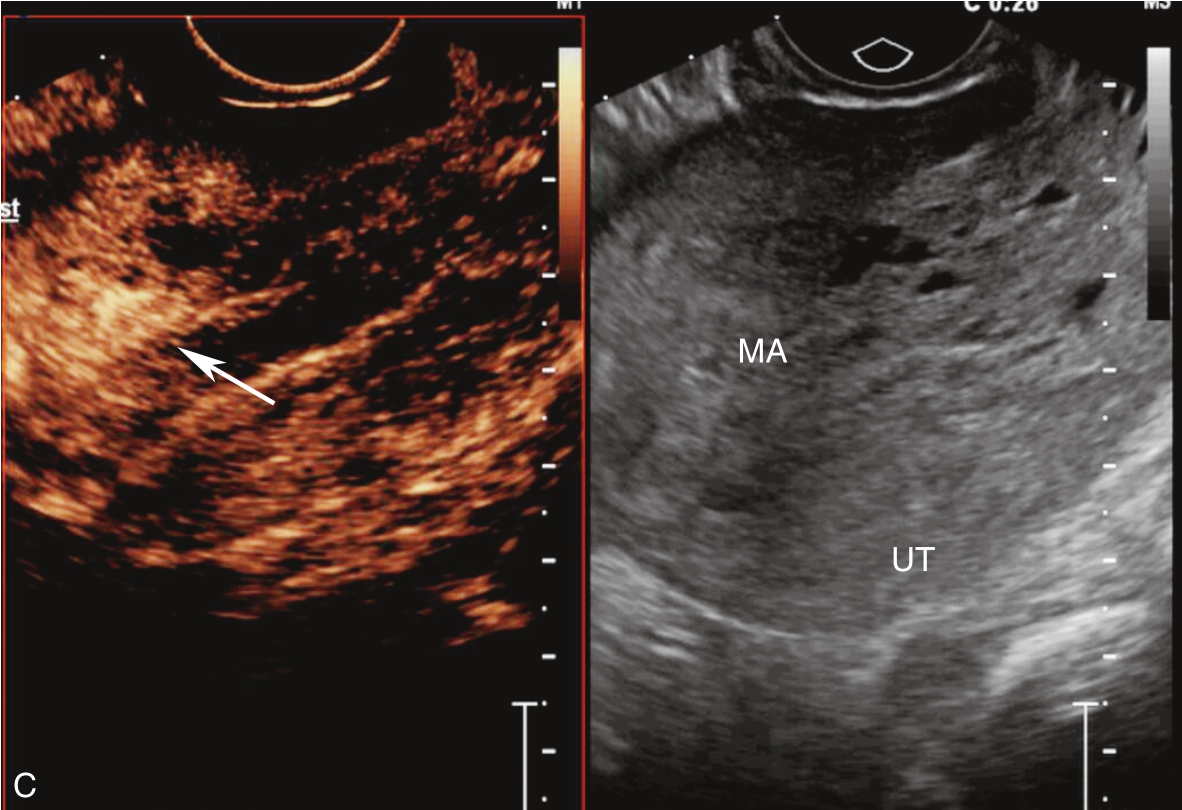

经阴道超声检查见图3-10-1。子宫前位,宫体大小5.6cm×6.9cm×6.5cm,宫腔内查见7.1cm×2.6cm×3.5cm不均质稍强回声,其内回声极不均匀,其内可见多个无回声区,最大无回声区的最大径为0.8cm,周边及其内探及丰富血流信号,该团块与子宫前壁关系密切。宫颈后唇查见囊性占位,大小为2.5cm×1.3cm×1.9cm,囊液清亮,未探及明显血流信号。双附件区未见确切占位。超声检查结果:宫腔内占位,宫颈后唇囊性占位。

图3-10-1 常规超声声像图

A.子宫矢状切面显示宫腔内稍强回声;B.子宫横断面显示宫腔内强回声;C.子宫矢状切面显示宫颈管内占位;D.宫颈管内占位的血流情况;E.宫腔占位的血流情况;F.宫颈囊性占位(箭头所示)。UT:子宫;C:宫颈;MA:肿物。